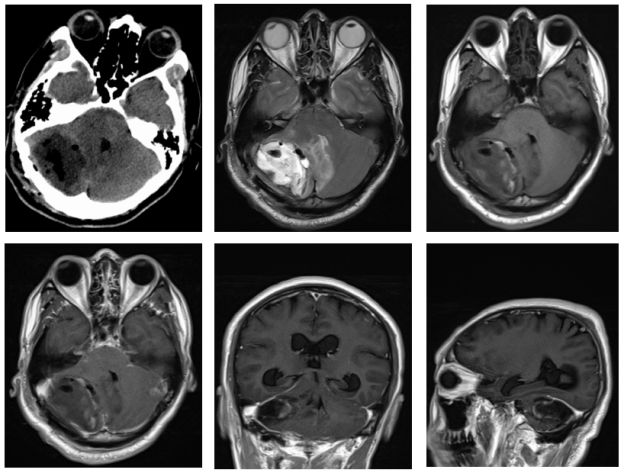

右侧小脑半球见团片状不均匀长T1长T2信号影,DWI局部高信号,增强扫描可见不均匀环形强化,病灶边界欠清,范围约为48mmX19mm,周围可见水肿带(图1)。影像学诊断:首先考虑感染性病变伴脑脓肿形成,肿瘤不能排除。MRS检查示:NAA明显下降,Cho峰升高,Cho/NAA比值增高。Cr峰降低,宽大LL峰出现,诊断考虑病变坏死明显,梗塞局部软化或脓肿(如寄生虫感染)可能,不支持脑肿瘤诊断(图2)。

图1. 右侧小脑半球见团片状不均匀长T1长T2信号影,DWI局部高信号,增强扫描可见不均匀环形强化,病灶边界欠清,范围为48mmX19mm,周围可见水肿带。

经抗感染治疗10天后,再次行腰穿检查,压力:120cmH2O,脑脊液澄清透明,有核细胞计数 2 /μL,红细胞计数 0.00 /μL,葡萄糖 4.04 mmol/L,蛋白质 41.50 mg/dL,氯 128.3 mmol/L,培养未见细菌、真菌生长。脑脊液寄生虫抗体检测亦未见明显异常。复查头颅MRI示:图3右侧小脑半球见团片状不均匀长T1长T2信号影,DWI呈高信号,增强扫描可见不均匀环形强化,病灶边界欠清,范围约为48mmX19mm,周围可见水肿带(图3)。诊断考虑:感染性病变伴脑脓肿形成,对照前片病灶液化、水肿略增加。

图3. 右侧小脑半球见团片状不均匀长T1长T2信号影,DWI呈高信号,增强扫描可见不均匀环形强化,病灶边界欠清,范围约为48mmX19mm,周围可见水肿带,对照前片病灶液化、水肿略增加。